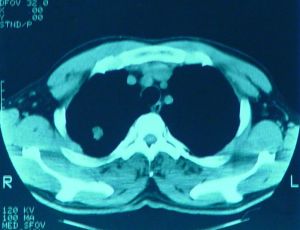

4.血源性肺膿腫多先有原發病灶引起的畏寒、高熱等全身膿毒血症的症狀。經數日至兩周才出現肺部症狀,如咳嗽、咳痰等。通常痰量不多,極少咯血。

1.胸部X線檢查是肺膿腫的主要診斷方法。由於膿腫有向不同葉蔓延的特點,可波及多葉甚至全肺。但如一開始就發生在上述以外的部位,要懷疑有特殊的病因,如腫瘤堵塞性膿腫或肺囊腫感染等。肺膿腫在各不同階段病理改變很大,X線也有很大不同。急性期(在1周內)為大片緻密模糊陰影,按葉段分布呈楔形,尖向肺門,外側緊貼胸廓,縱隔或葉間胸膜面;在治療下,陰影改變較快。當膿腫與支氣管相通時,即出現空腔,由於引流支氣管多不通暢,加上體位因素,膿液不能完全排出,片上常見液平面。因壁厚,加上周圍仍有炎症,腔外有厚層,雲霧狀炎症浸潤影,慢性的周圍還有纖維化。空腔大小、形態不一,可呈圓形、橢圓形或不規則形,不少是多房的。經治療後如好轉,則空腔漸縮小、消失,留下纖維條索狀陰影及胸膜肥厚影。

2.CT檢查斷層(包括CT)可更好了解病變範圍、部位、空腔情況。少數膿腫內膿液未排出,表現為圓形塊影,但在可見內有小空洞,真正呈實塊的不多,易誤為腫瘤。纖維化明顯的肺體積縮小,支氣管完全閉塞可有肺不張。可

見葉間胸膜增厚。膿腫破向胸腔形成膿胸或膿氣胸,片上有相應改變。